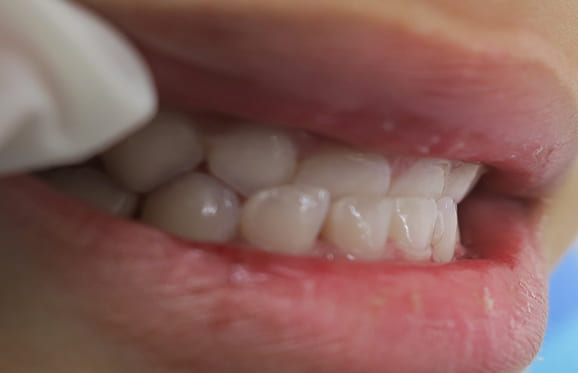

● 歯根が折れ保存不可の歯を抜歯して、そのスペースに八重歯を並べた症例

藤沢デンタルオフィスの虫歯や破折で抜歯後の部分矯正